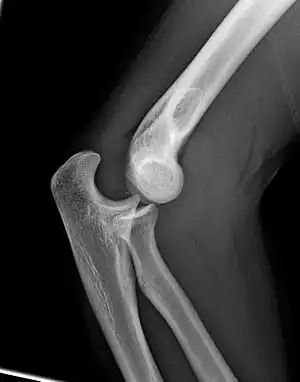

| Lateral X ray of a dislocated right elbow. | |

| Diagnostic method | Supported by X-rays[2] |

Initial imaging is generally with plain X-rays.[2] CT scan may be used to detect subtle fractures or find fragments of bone preventing reduction.[2] MRI may be useful to detect injury to ligaments.[2]